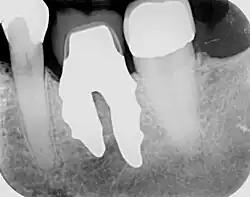

A root-analogue dental implant (RAI) – also known as a truly anatomic dental implant, or an anatomical/custom implant – is a medical device to replace one or more roots of a single tooth immediately after extraction.[1] In contrast to common titanium screw type implants, these implants are custom-made to exactly match the extraction socket of the specific patient. Thus there is usually no need for surgery.[2]

As the root analogue dental implant matches the dental alveolus (tooth socket) it can only be placed immediately after the tooth extraction. If the tooth has been already lost and the soft and hard tissue is already healed, an RAI can no longer be placed.[1]

RAIs are custom made to perfectly fit the tooth socket of a specific patient immediately after tooth extraction. Therefore every implant is unique. As an optimised root-form it is much more than a simple 1:1 replica of a tooth. Since it exactly fills the gap left after the tooth is extracted, surgery is rarely needed. The implant can be produced from a copy of the extracted tooth, an impression of the tooth socket, or from a CT scan or CBCT scan.[7] The advantage of a CBCT scan is that the implant can be produced before extraction. With the former methods, it takes one or two days to fabricate an implant.

- Natural form: a custom milled anatomic implant replicates the natural form of a tooth, so it simply fits into the tooth socket. Like the original tooth, a root analogue implant can have single- and multi-rooted forms.